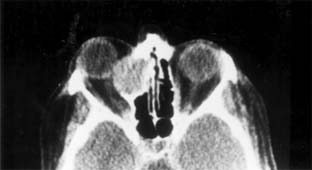

Chapter 13: Orbit DISEASES & DISORDERS OF THE ORBIT INFLAMMATORY DISORDERS 1. GRAVES' OPHTHALMOPATHY The most common cause of unilateral or bilateral proptosis in adults or children is Graves' disease. The terminology used to describe ocular involvement in thyroid disease is often confusing. Graves' ophthalmopathy, dysthyroid ophthalmopathy, and dysthyroid eye disease are interchangeable terms. Some degree of ophthalmopathy-usually mild-occurs in a high percentage of hyperthyroid patients. Severe infiltrative orbital myopathy with significant proptosis and restricted motility occurs in about 5% of cases of Graves' disease (Figure 13-3). This severe form, however, can also occur with hypothyroidism or with no detectable thyroid abnormality, in which case the term ophthalmic Graves' disease may be used. Thyroid ophthalmopathy is thought to be an autoimmune disease. It is often seen in autoimmune (Hashimoto's) thyroiditis. Antithyroglobulin, antimicrosomal, and other antibodies can usually be demonstrated, but their role in pathogenesis is in question. Clinical Findings Proptosis associated with thyroid disease is characterized by lid retraction, which serves to distinguish it from other causes of proptosis. Lagophthalmos results from proptosis and lid retraction, and corneal exposure is a factor even in mild cases. Ocular myopathy usually begins with lymphocytic infiltration and edema of the rectus muscles. In time, the inflamed muscles may become fibrotic and permanently restricted. The eye may be tethered so as to raise the intraocular pressure when it is measured in upgaze. Diplopia usually begins in the upper field of gaze because of infiltrative myopathy involving the inferior rectus muscle. All extraocular muscles may eventually be involved, and there may be no position of gaze free of diplopia. The extraocular muscles may become massively enlarged and-in addition to restricting eye movement-may compress the optic nerve. Compressive optic neuropathy is most common with enlargement of the posterior aspect of the muscles that occurs without severe proptosis. Early signs include an afferent pupillary defect, impairment of color vision, and slight loss of visual acuity. Blindness is liable to occur if compression is unrelieved. Treatment The goal of treatment of Graves' ophthalmopathy is initially to maintain corneal protection. As the disease progresses it becomes necessary to address the problems of diplopia, proptosis, and compressive optic neuropathy. Management of severe cases is difficult and multidisciplinary. An endocrinologist should manage the thyroid status, optimal control being crucial to ameliorating the orbital disease. Oral cortico-steroids (prednisone, 60-100 mg/d) may be helpful in controlling the acute phase of infiltrative myopathy. Complications and side effects limit the use of corticosteroids in long-term maintenance. Orbital radiation is effective during the active phase of the disease. Soft tissue signs of swelling and chemosis are usually relieved. Diplopia and proptosis may be improved. Early compression neuropathy may also be relieved by radiation therapy, but neuropathy unresponsive to medical management is an indication for surgical decompression of the orbit. Several approaches have been devised to expand the orbital volume by fracture of the bony walls, usually the orbital floor into the maxillary sinus and the medial wall into the ethmoid sinus, along with removal of the lateral orbital wall in some cases. Proptosis can be reduced by surgery, but there is a risk of intractable diplopia and a lesser risk of orbital infection. For these reasons, decompression for cosmetic reasons is not routinely performed. Eyelid retraction is often more disturbing than proptosis-both functionally, because of exposure keratitis, and cosmetically. Decompression may relieve lid retraction, but correction of the retraction camouflages proptosis to some extent. Lid retraction is corrected by surgery. The upper and lower lid retractors (aponeurosis and sympathetic muscles) can be lengthened by inserting a spacer such as eye bank sclera. Small amounts (2 mm) of lid retraction can be corrected by simply disinserting the retractors from the upper tarsal border. Strabismus surgery should not be undertaken until the myopathy has stabilized. The adjustable suture technique is useful. Most patients can achieve at least a small area of binocular single vision in a useful position of gaze. Torsional diplopia, the result of oblique muscle involvement, complicates management. Some patients have intractable diplopia despite all attempts at correction. 2. PSEUDOTUMOR A frequent cause of proptosis in adults and children is inflammatory pseudotumor. The term "pseudotumor" was coined to indicate a nonneoplastic process that produces the sentinel sign of an orbital neoplasm, ie, proptosis. In some cases there is an associated systemic vasculitis, such as Wegener's granulomatosis. The site of inflammation is usually diffuse and not amenable to excision. The process can involve any orbital structure (eg, myositis, dacryoadenitis, lymphogranuloma) or cell type (eg, lymphocytes, fibro-blasts, histiocytes, plasma cells). Onset is usually rapid, and pain is often present. Pseudotumor is usually unilateral; when both orbits are involved, it is more often a manifestation of vasculitis. The differential diagnosis includes Graves' ophthalmopathy and orbital lymphoma. Treatment with systemic nonsteroidal anti-inflammatory drug (NSAID)s, systemic corticosteroids, or radiation is usually effective. Surgery often exacerbates the inflammatory reaction. ORBITAL INFECTIONS 1. ORBITAL CELLULITIS (Figure 13-4) Orbital cellulitis is the most common cause of proptosis in children. Immediate treatment is essential. Fortunately, the diagnosis usually is not difficult, because the clinical findings are characteristic. Although most cases occur in children, aged and immunocompromised individuals may also be affected. Trauma may be responsible for introduction of contaminated material into the orbit through the skin or paranasal sinuses. In the preantibiotic era, orbital cellulitis frequently led to blindness or death resulting from septic cavernous sinus thrombosis. The orbit is surrounded by the paranasal sinuses, and part of their venous drainage is through the orbit. Most cases of orbital cellulitis arise from extension of sinusitis through the thin ethmoid bones. The organisms usually responsible are those most frequently found in sinuses: Haemophilus influenzae, Streptococcus pneumoniae, other streptococci, and staphylococci. Clinical Findings Preseptal cellulitis is the most common presentation. CT scan or MRI is helpful in distinguishing between pre- and postseptal involvement as well as identifying and localizing an orbital abscess or foreign body. Plain x-rays alone can only identify the presence of sinusitis. It is important to distinguish between preseptal and orbital infections. Both present with edema, erythema, hyperemia, pain, and leukocytosis. Chemosis, proptosis, limitation of eye movement, and reduction of vision indicate deep orbital involvement. Extension to the cavernous sinus may cause bilateral involvement of cranial nerves II-VI, with severe edema and septic fever. Erosion of the orbital bones may cause brain abscess and meningitis. In children, few orbital diseases develop as rapidly as cellulitis. Confusion may exist with rhabdomyosarcoma, pseudotumor, and Graves' ophthalmopathy. Treatment Treatment should be initiated before the causative organism is identified. As soon as nasal, conjunctival, and blood cultures are obtained, intravenous antibiotics should be administered. Initial antibiotic therapy should cover staphylococci, H influenzae, and anaerobes. Posttraumatic cellulitis-especially following animal bites-must be covered for gram-negative and gram-positive bacilli. Hot compresses help localize the inflammatory reaction. Nasal decongestants and vasoconstrictors help drain the paranasal sinuses. Early surgical drainage is indicated in suppurative preseptal cellulitis. MRI is useful in deciding when and where to drain an orbital abscess. Most cases respond promptly to antibiotics. Those that do not may require drainage of the paranasal sinuses. Early consultation with an otolaryngologist may be helpful. 2. MUCORMYCOSIS Diabetics and immunocompromised patients have a propensity to develop severe and often fatal fungal infections of the orbit. The organisms are of the Zygomycetes group, which have a tendency to invade vessels and create ischemic necrosis. Infection usually begins in the sinuses and erodes into the orbital cavity. A necrotizing reaction destroys muscle, bone, and soft tissue, frequently without causing signs of orbital cellulitis. The patient is usually quite ill and presents with pain and proptosis. Examination of the nose and palate often reveals a necrotic area of mucosa, a smear of which shows broad branching hyphae. Without treatment, the infection gradually erodes into the cranial cavity, resulting in meningitis, brain abscess, and death usually within days to weeks. Treatment is difficult and often inadequate. It consists of correction of the underlying disease combined with surgical debridement and administration of amphotericin B intravenously. Recurrences are common. CYSTIC LESIONS INVOLVING THE ORBIT 1. DERMOID Dermoids are not true neoplasms but benign choristomas arising from embryonic tissue not usually found in the orbit. Orbital dermoids arise from surface ectoderm and often contain epithelial structures such as keratin, hair, and even teeth. Most are cystic and filled with an oily fluid that can incite a severe inflammatory reaction if liberated into the orbit. Most dermoids occur in the superior temporal quadrant of the orbit, but they can occur at any bony suture line. X-rays show a sharp, round bony defect from the pressure of a slowly growing mass affixed to the periosteum. Epidermoid cyst is a superficial keratin-filled mass, usually near the superior orbital rim. It may be congenital or posttraumatic. Excision is usually not difficult. A dermolipoma is a solid mass of fatty material that occurs below the conjunctival surface. Hair growth on the overlying conjunctiva is not uncommon. Dermolipomas are often much larger than they appear to be, and excision may cause considerable damage to vital structures. If treatment is necessary, limited excision is usually advised. 2. SINUS MUCOCELE The proximity of the orbit to the paranasal sinuses may lead to invasion of the bony walls and extension of an obstructed sinus into the orbit. Plain x-ray will usually make the diagnosis, but CT or MRI may be required to differentiate sinus mucocele from dermoid cyst and to define the extent of the lesion (Figure 13-5). Otolaryngologic and neurosurgical assistance may be necessary for surgical removal. 3. MENINGOCELE Erosion of the meninges into the orbital cavity through a congenital dehiscence in the bony sutures creates a cystic mass filled with cerebrospinal fluid known as a meningocele. Both brain and meninges are frequently included in a meningoencephalocele. The resultant fluctuant mass in the superior medial orbit typically enlarges with Valsalva's maneuver. Most cases are present at birth, but those arising from the sphenoid bone may not become apparent until adolescence. VASCULAR ABNORMALITIES INVOLVING THE ORBIT 1. ARTERIOVENOUS MALFORMATION Arteriovenous malformations are an uncommon cause of proptosis. Varices produce intermittent prop-tosis, sometimes associated with pain and transient reduction of vision. Some degree of proptosis can be induced with Valsalva's maneuver or by placing the head in a dependent position. MRI scan is usually diagnostic, and venography is seldom indicated. Surgery is the only method of treatment available and is fraught with hazard. Morbidity following eradication of the varix may jeopardize visual function. Most varices are best left untreated unless vision is at risk. 2. CAROTID ARTERY-CAVERNOUS SINUS FISTULA Carotid artery-cavernous sinus fistulas with high-flow shunts are easily diagnosed. Although sometimes occurring spontaneously, they usually follow trauma. Physical signs include severe congestion and chemosis, with pulsating proptosis and a loud bruit. Low-flow shunts (dural carotid cavernous sinus fistula) are usually spontaneous and often misdiagnosed. Mild congestion, venous engorgement and arterialization, elevated intraocular pressure, mild proptosis, and a faint bruit are the usual features. Diagnosis is by contrast MRI or subtraction angiography, and treatment is by selective intra-arterial or transvenous embolization. Page 2 of 7 10.1036/1535-8860.ch13 |